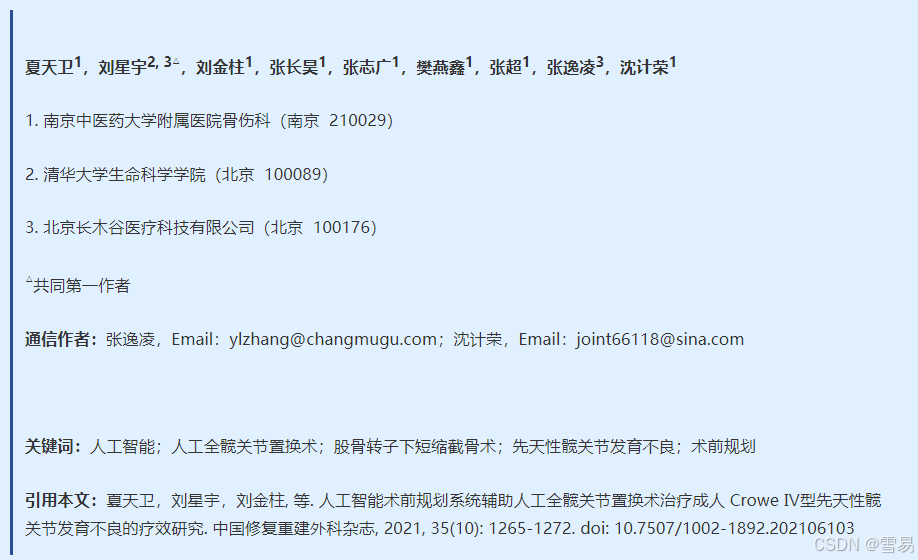

Crowe Ⅳ型 DDH 属于高度脱位,考虑到术中必要时须行 SSOT 以利于股骨头复位至真臼内,故手术均采用常规后外侧入路。术前摄标准骨盆正位 X 线片及双髋关节 256 排 CT 平扫,扫描范围为整个骨盆及股骨小转子下 15 cm,扫描层厚0.8 mm。将扫描获得数据以 DICOM 格式导入AIHIP 软件,软件可自动识别、分析手术部位,完成术前规划(图 1)。

图 1 AIHIP 系统术前规划流程图